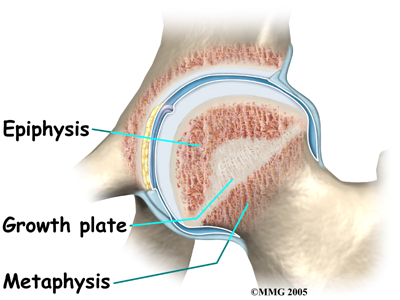

In the growing child, there are special structures at the end of most bones called growth plates. The growth plate is sandwiched between two special areas of the bone called the epiphysis and the metaphysis. The growth plate is made of a special type of cartilage that builds bone on top of the end of the metaphysis and lengthens the bone as we grow. In the hip joint, the femoral head is one of the epiphyses of the femur.

The capital femoral epiphysis is somewhat unique. It is one of the few epiphyses in the body that is inside the joint capsule. (The joint capsule is the tissue that surrounds the joint.) The blood vessels that go to the epiphysis run along the side of the femoral neck and are in danger of being torn or pinched off if something happens to the growth plate. This can result in a loss of the blood supply to the epiphysis.

Perthes disease results when the blood supply to the capital femoral epiphysis is blocked. There are many theories about what causes this problem with the blood supply, yet none have been proven. There appears to be some relationship to nutrition as children who are malnourished are more likely to develop this condition.

Whatever the true cause of ischemia (lack of blood to the area), the result is bone death (called necrosis) of the femoral head. Without a normal blood supply, the bone loses its strength and shape. The loss of bone density and softening of the head result in a femoral head that is misshaped. With the hip supporting the weight of the body, tiny microfractures in the soft, necrotic bone fail to heal. This is another reason why normal wear and tear results in a deformity.